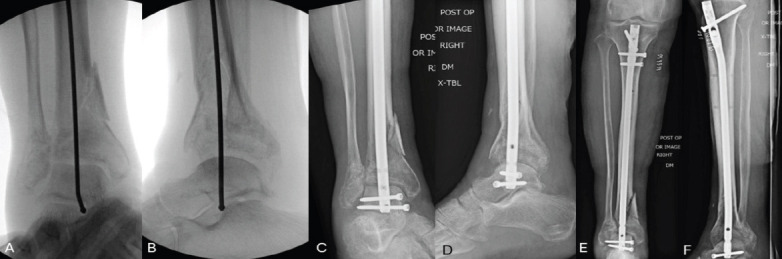

Case report: A 64-year-old female with a history of chronic obstructive pulmonary disease, hypertension, and a significant smoking history presented with a right tibial pilon and distal fibula fracture following a fall down the stairs. Due to her medical comorbidities and poor soft tissue envelope, she was at high risk for complications with ORIF. After discussing multiple treatment options, she elected to proceed with a tibiotalar intramedullary nail to optimize function while minimizing surgical morbidity. The procedure was performed using a suprapatellar approach, and an 8mm nail was inserted to preserve bone stock and future surgical options. Postoperatively, she progressed well, achieving full fracture healing by 9 months with minimal pain and functional independence. She declined further surgical intervention for hardware removal or ankle fusion, reporting satisfaction with her outcome.